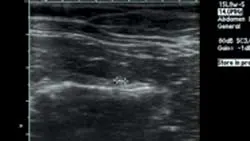

Static left renal disease and mild hydronephrosis of the right kidney with proximal hydroureter were evident on renal ultrasonography (Figure 3, right: Ultrasound of the right kidney showing pelvic dilation. View larger image). Renal calculi were present bilaterally.